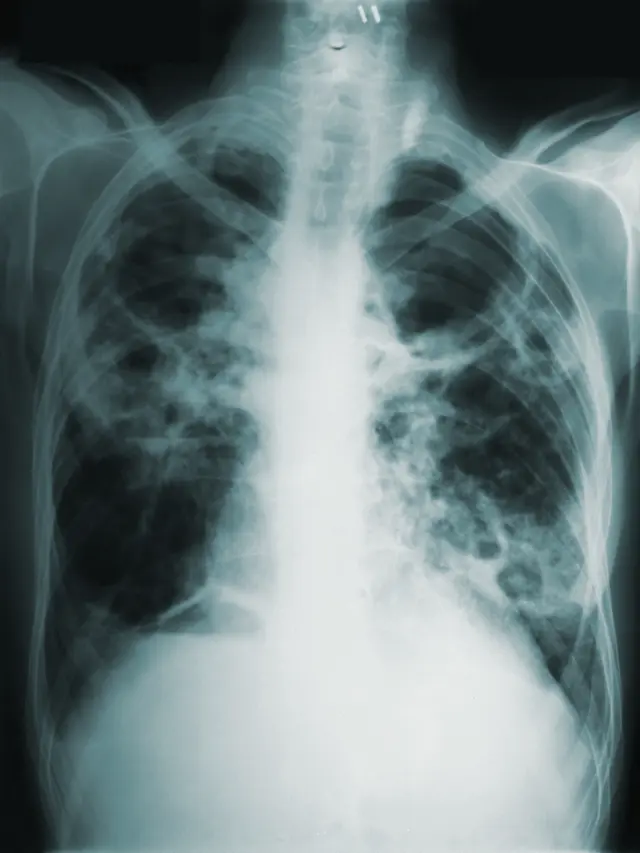

Fimela.com, Jakarta Tuberkulosis atau yang dikenal dengan singkatan TB adalah salah satu penyakit menular yang disebabkan oleh bakteri Mycobacterium Tuberculosis. Penyakit ini pada dasarnya akan menyerang paru-paru. Bukan hanya itu, terkadang penyakit ini juga dapat menyerang organ tubuh lainnya, seperti tulang, ginjal, dan otak. Maka dari itu penanganan dan edukasi tentang penyakit ini tidak kalah pentingnya untuk disuarakan.

Berdasarkan data yang disebarkan oleh Ayosehat.kemenkes.go.id, mengungkapkan bahwa Indonesia menempati peringkat kedua setelah India terkait penyakit Tuberkulosis atau TBC, yaitu dengan jumlah kasus sebanyak 969 ribu dan 93 ribu kematian per tahunnya. Angka kematian ini bisa gambarkan seperti 11 kematian per jamnya. Bukan hanya itu, berdasarkan data yang mengutip dari Global TB report 2022 mengungkapkan bahaya penyakit TB ini banyak sekali menyerang kelompok usia produksi terutama umur 45 sampai dengan 54 tahun.

Mengutip dari CDC.gov mengungkapakan bahwa TBC umunya menyebar melalui udara dari orang ke orang. Ketika seseorang yang terinfeksi TBC paru atau tenggorokan batuk, berbicara, tertawa, bernyanyi, atau bersin, mereka dapat melepaskan kuman TBC ke udara. Orang lain yang berada di dekat penderita TBC dapat menghirup kuman TBC ke paru-parunya.